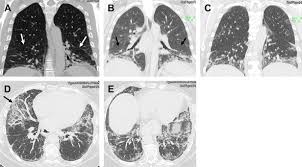

World map of Antisynthetase syndrome. ICD-10-CM Diagnosis Code G463 convert to ICD-9-CM Brain stem stroke syndrome. Antisynthetase syndrome Clinical manifestations Prevalence Myositis 90 Interstitial lung disease 60 Arthritis 50 Raynauds phenomenon 40 Fevr20 Mechanics hands 30 Lung involvement.

Antisynthetase syndrome Disease definition A rare idiopathic inflammatory myopathy IIM characterized principally by myositis generally symmetrical arthritis and interstitial lung disease ILD in association with serum autoantibodies to aminoacyl-transfer RNA synthetases anti-ARS. ICD-10-CM Diagnosis Code S14122D convert to ICD-9-CM Central cord syndrome at C2 level of cervical spinal cord subsequent encounter. Rüegg CA et al.

Antisynthetase syndrome is a set of symptoms that typically occur for patients who have myositis together with one of several specific autoantibodies known as antisynthetase antibodies. 816 Reticuloendothelial and immunity disorders without ccmcc.